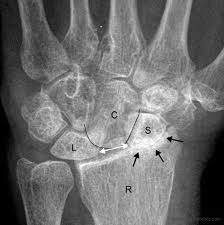

This X-ray shows the normal orientation of the bones in the wrist.